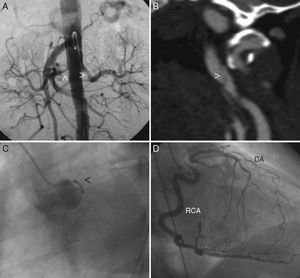

We submitted information for a woman of 43 years, with a medical history of systemic arterial hypertension secondary to bilateral stenosis of renal arteries (Fig. 1A) and cerebral ischaemic attack due to dissection of left carotid artery (Fig. 1B). She was sent for assessment due to effort angina. Coronary catheterization showed proximal occlusion of the anterior descending artery (Fig. 1C) with collateral flow from the right coronary artery (Fig. 1D). Aortography of supra-aortic trunks was normal. There was no evidence of anaemia, thrombocytopenia, or alterations in acute phase reactants or autoimmunity.

(A) Abdominal aortography evidencing proximal stenosis at both renal arteries level (arrowhead). (B) Angiography by computed tomography where it is possible to observe left carotid artery dissection (arrowhead). (C) Left coronary catheterization (left anterior oblique) where only a poor-developed circumflex artery can be seen (arrowhead). (D) Right coronary catheterization (left anterior oblique) that evidences a dominant right coronary artery (RCA) that fills for collateral circulation of descending artery (DA), which is occluded at proximal level.